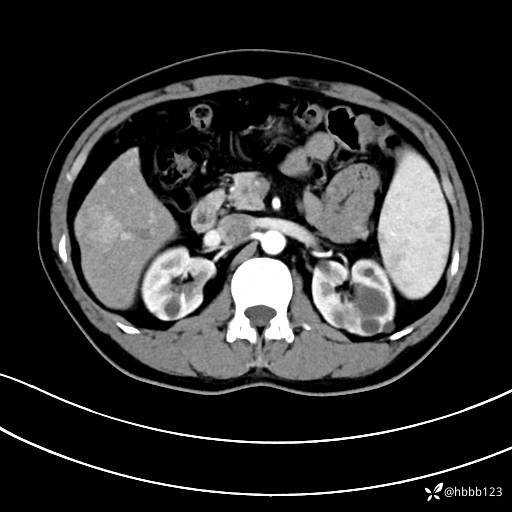

门诊完善上腹部CT平扫+增强。

平扫: